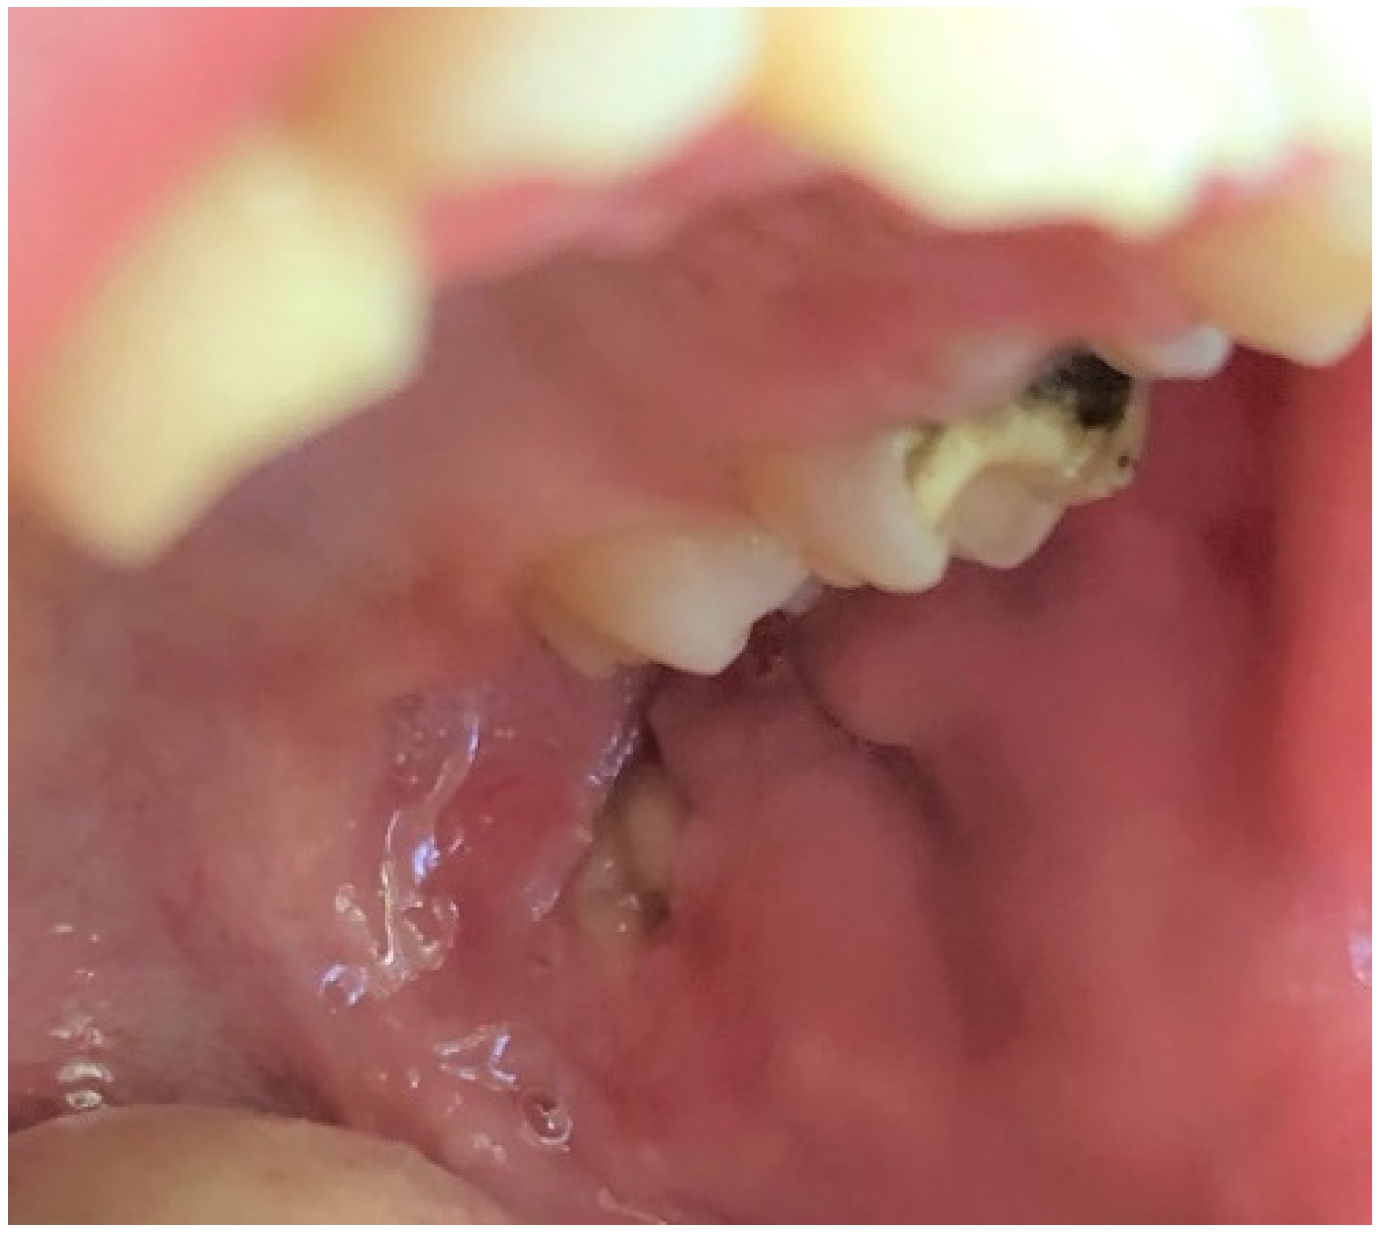

Mucoceles are a common alteration of minor salivary glands due to trauma followed by obstruction of the salivary gland duct which effects cystic swelling, as seen in Figure 4 [22]. In this study they were diagnosed as the second most prevalent OML among the entire group of subjects (10.5%) among girls and school-age children. A similar incidence (13.5%) was revealed by Sousa et al. [23]. It was also the third most common lesion in adolescents, and one of the least frequent among preschool children (only two cases). This is not surprising, since many studies show that such disorders are often observed in the second decade of life and rarely in infants [24,25]. In our research, this pathology was more frequent among girls than boys, similar to observations made by Vale et al. [26]. In the same study, a histological revision of 315 diagnoses of pediatric patients revealed a very high incidence of mucocele, amounting to 33.3%. Other analyses by Wang et al. [27] and Lima et al. [18] also showed a high frequency of mucoceles, 24.5% and 17.2%, respectively. On the other hand, there are also other reports showing a lower prevalence of mucoceles in the pediatric population, but even in these studies with a lower incidence, mucoceles were always among the most commonly diagnosed OMLs [1,2,3,10,20,28,29,30].

Figure 4.

Mucocele on the lower lip of an adolescent girl. Typical dome-shaped fluctuant mucosal swelling. The lower lip is the most common site for this lesion to develop due to the relative ease of traumatizing this area.